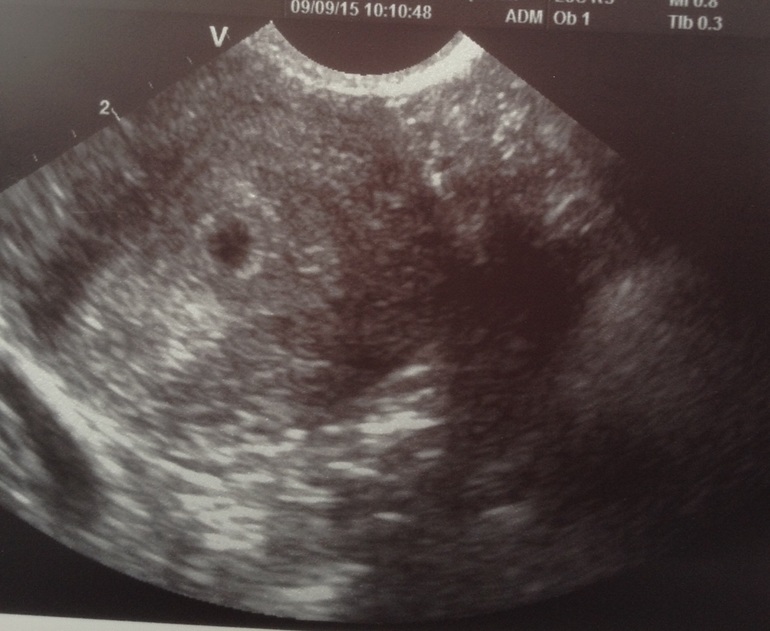

Сегодня было волнительное утро, первое УЗИ, я конечно понимаю, что еще рано, но во-первых так сказала врач, через неделю после задержки, чтобы подтвердить маточную беременность, во-вторых, послезавтра я уезжаю и чтобы мои нервы были спокойны, сделать УЗИ нужно. Плодное яйцо в матке, диаметром 5мм, сердцебиения пока нет, но для моего срока два врача сказали, что это нормально, сегодня 21 ДПО, а после имплантации примерно 13 день. Сдала еще раз анализы на прогестерон и хгч, там же в медицинском центре. Завтра будет результат. На УЗИ теперь пойду 25 сентября, сердечко уже точно должно биться. По поводу моих колик по бокам, врач сказала, что это может быть, просто тянутся связки. Единственное - маленькое желтое тело, но я пью Дюфастон, поэтому надеюсь, что волноваться не стоит

Сегодня созванивалась со своим врачом, консультировалась по поводу анализов, она назначила Дюфастон 2 раза в день по 1 таблетке, продолжать пить Фемибион 1 и начать пить витамин Е по одной таблетке в день по 400 мг. Еще что-то горло приболело, полоскаю ромашкой. Жду среду - 9 число, первое узи